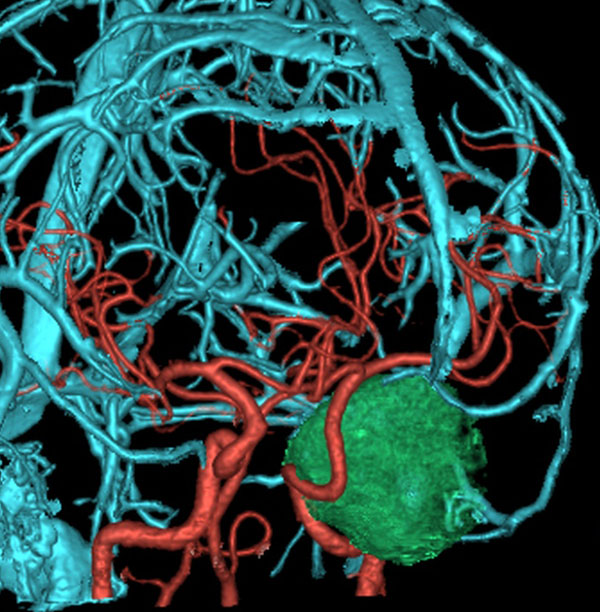

7歳の時に偶然発見された左海綿静脈洞外壁の類皮のう胞 dermoid cystで,多数の脳神経と皮膜が癒着するものです。この腫瘍は先天性の腫瘍なのでおそらく生まれた時からあったものです。10歳の時に手術摘出しました。画像は22歳の時の手術前のものです。何故2回も部分摘出したのかは,この類皮のう胞というのは脳組織や髄膜や脳神経にベトベト癒着してくっつく性質があるからです。海綿静脈洞内にある脳神経と剥離できませんでした。でも初回手術から12年無症状でしたし,2回目の手術後も無症状です。

左側の画像はガドリニウム増強のT1強調MRIです。壁が厚いと造影剤で増強されることがありますが,この壁はとて硬いです。

時には毛が生えていてゴムのように硬い鳥皮のようなものもあります。そういうのは周囲組織を損傷しないと剥がせません。

この画像は拡散強調画像 DWI と言います。左が術前,右が術後です。拡散強調画像 DWIで強い高信号になるのが特徴です。しかし,類表皮のう胞でも高信号になるので注意を要します。

のう胞壁を残したので,さらに5年後に急速に大きくなりました。本人も27歳になり,仕方がないのでよくよく相談して,のう胞ごと全摘出しました。これで治った,と思える手術です。たくさんの脳神経に癒着していました。でも幸い,大ごとにはならなくて,額の感覚が少し低下,左目から涙が出ない,左のまぶたが少し下がっている(軽度の眼瞼下垂)くらいですみました。通常は左目の機能を完全に失う手術です。

前床突起硬膜あたりから発生したもの

16歳で無症状で発見されました。左前床突起の硬膜に強く癒着していたものです。開頭手術で全摘出したのですが,左シルピウス列には油性のdebrisが散在していてすでにruptureがありました。内頸動脈,前大脳動脈,中大脳動脈には高度に癒着があり,ハサミで動脈壁から切り離すという危険な摘出でした。類皮のう胞は動脈や脳と高度に癒着を生じる腫瘍だと,術前に覚悟しなければなりません。取り残しての再手術ではさらに癒着と肉芽組織との戦いになります。

この部位は取り残して再発すると,内頚動脈や前大脳動脈を切断する羽目にもなるので,何としても1回目で全摘出します